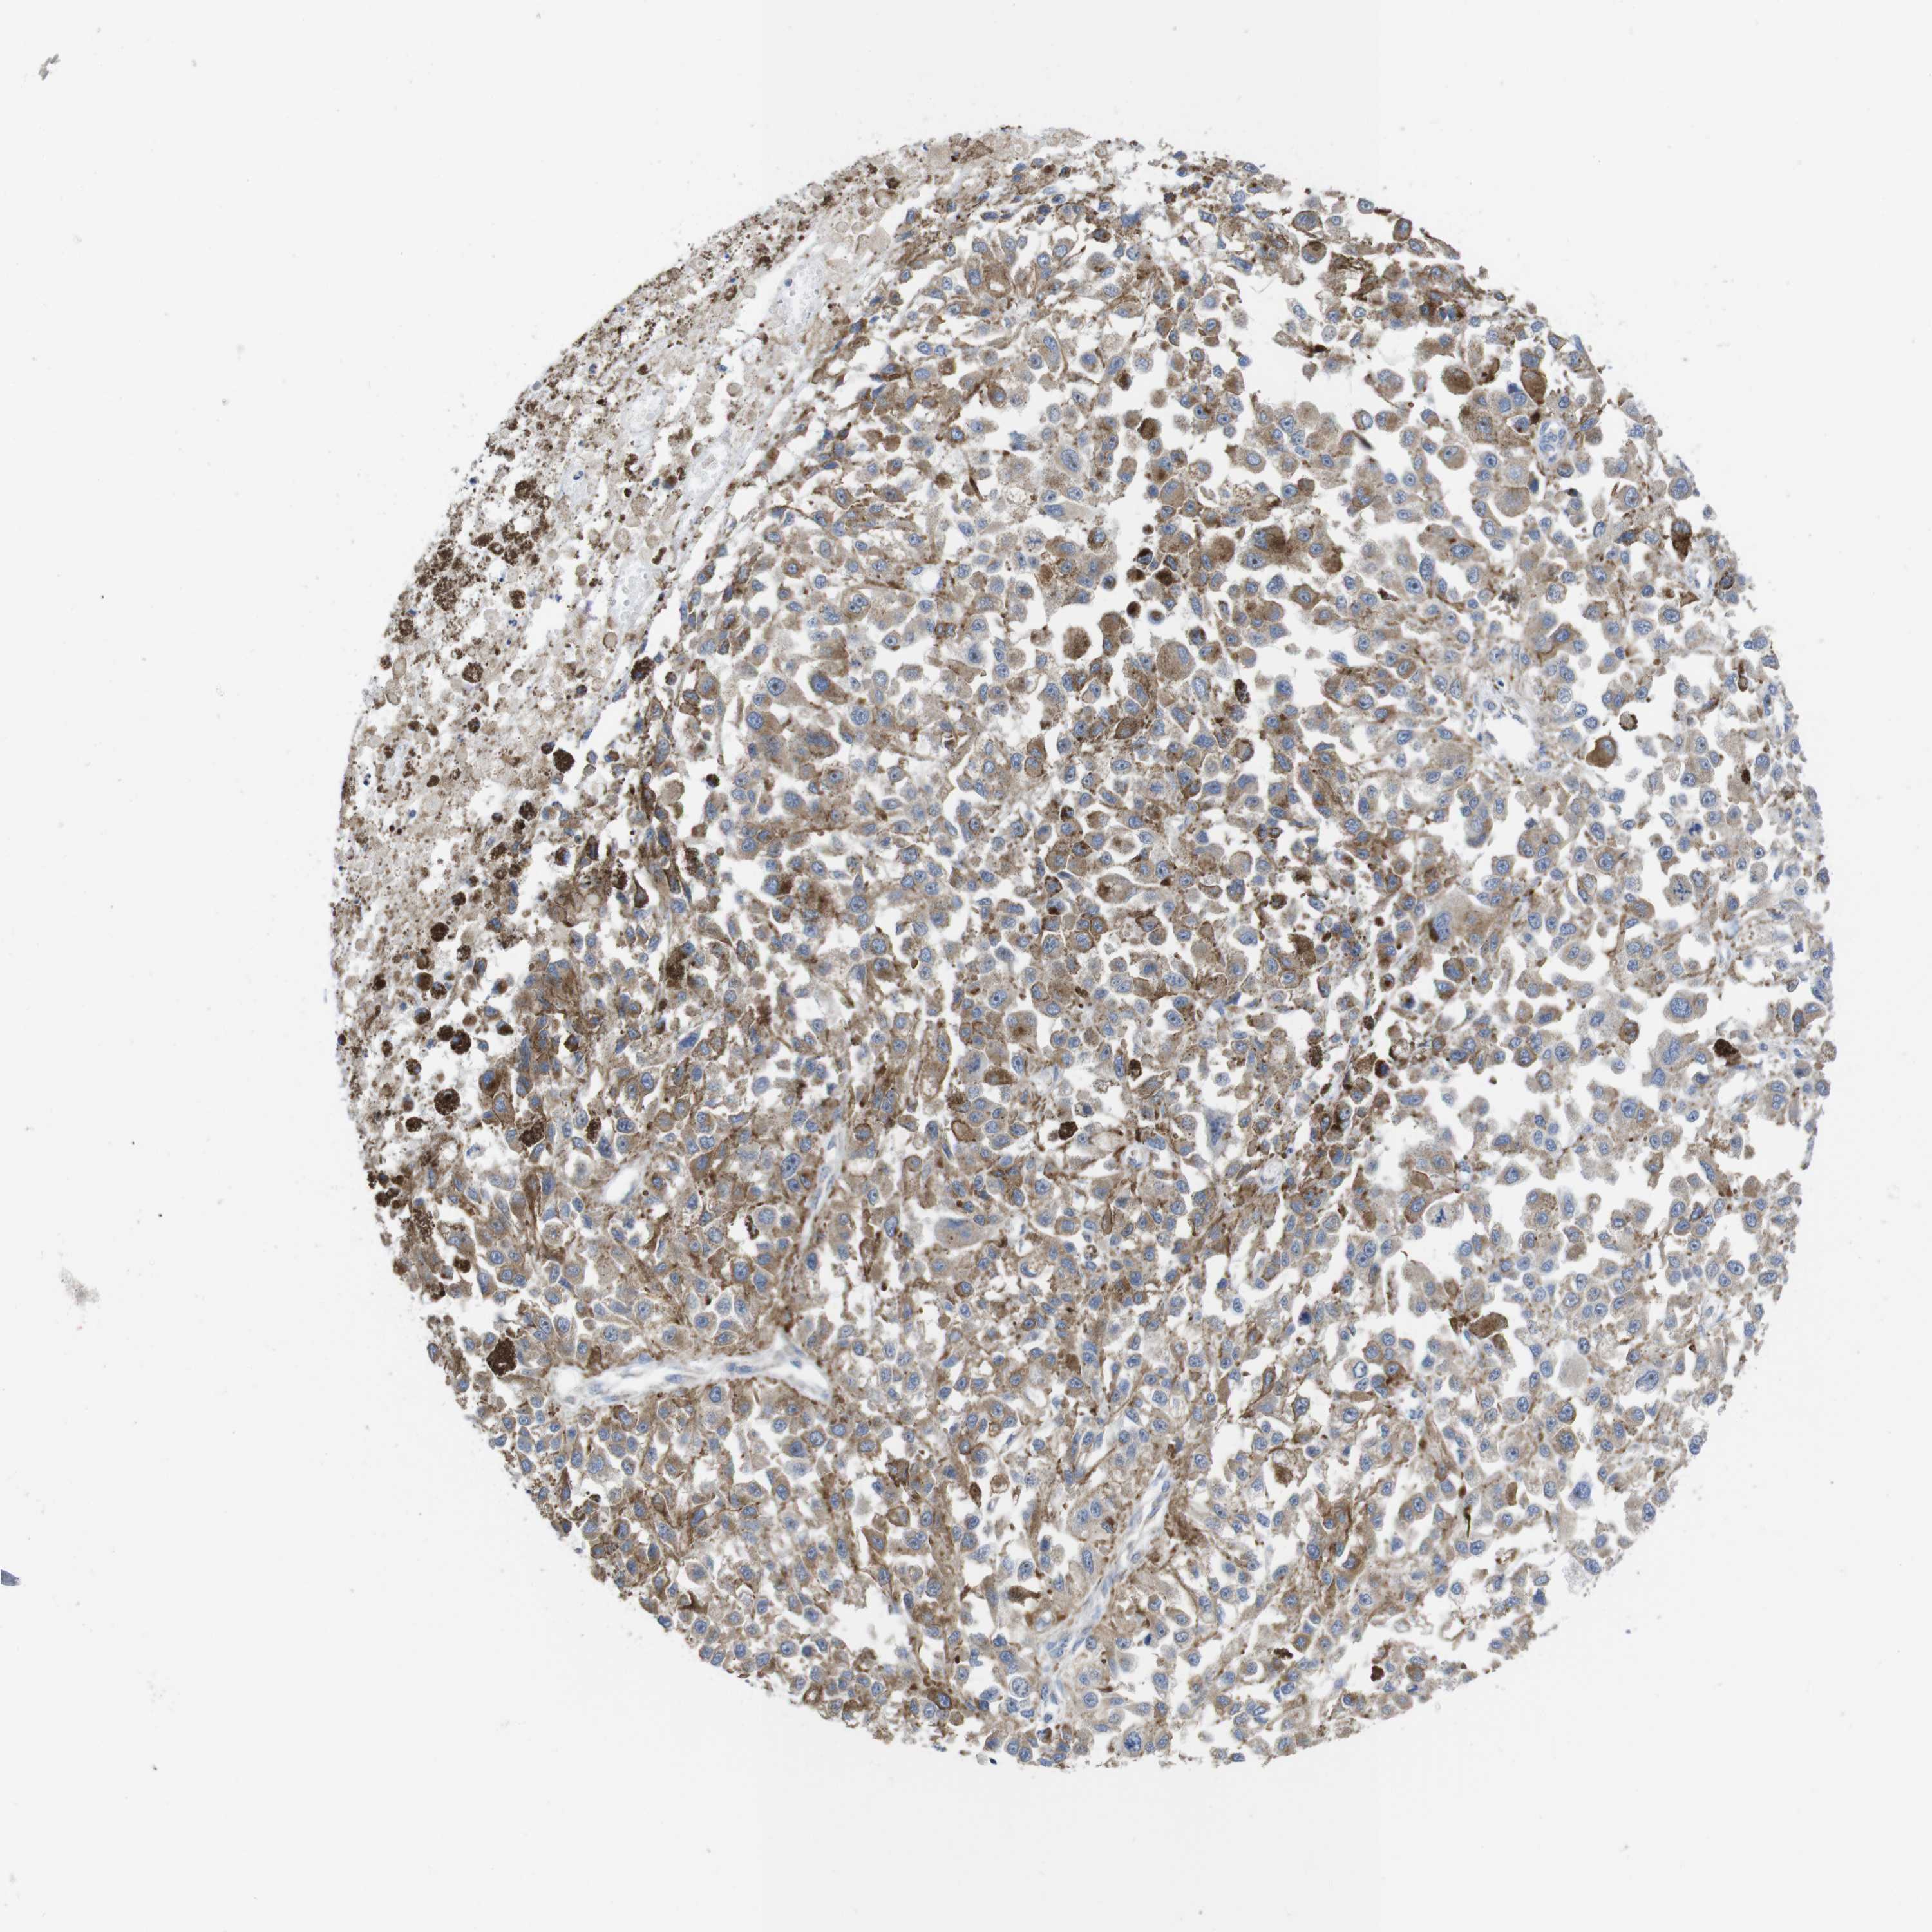

MELANOMA - Protein expressioni

A mouse-over function shows sample information and annotation data. Click on an image to view it in a full screen mode. Samples can be filtered based on level of antibody staining by selecting one or several of the following categories: high, medium, low and not detected. The assay and annotation is described here.

Note that samples used for immunohistochemistry by the Human Protein Atlas do not correspond to samples in the TCGA dataset.

Antibody stainingi

Antibody staining in the annotated cell types in the current human tissue is reported as not detected, low, medium, or high, based on conventional immunohistochemistry profiling in selected tissues. This score is based on the combination of the staining intensity and fraction of stained cells.

Each image is clickable and will lead to virtual microscopy that enables deeper exploration of all samples and also displays staining intensity scores, fraction scores and subcellular localization as well as patient and tissue information for each sample.

Antibody HPA014717

Antibody HPA024110

Staining

High

Medium

Low

Not detected

Intensity

Strong

Moderate

Weak

Negative

Quantity

>75%

75%-25%

<25%

None

Location

Nuclear

Cytoplasmic/membranous

Cytoplasmic/membranous,nuclear

Malignant melanoma, NOS

Malignant melanoma, Metastatic site